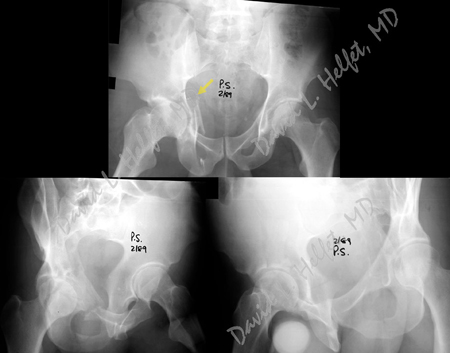

Radiographs reveal a right-sided Anterior Column Posterior Hemitransverse acetabular fracture.